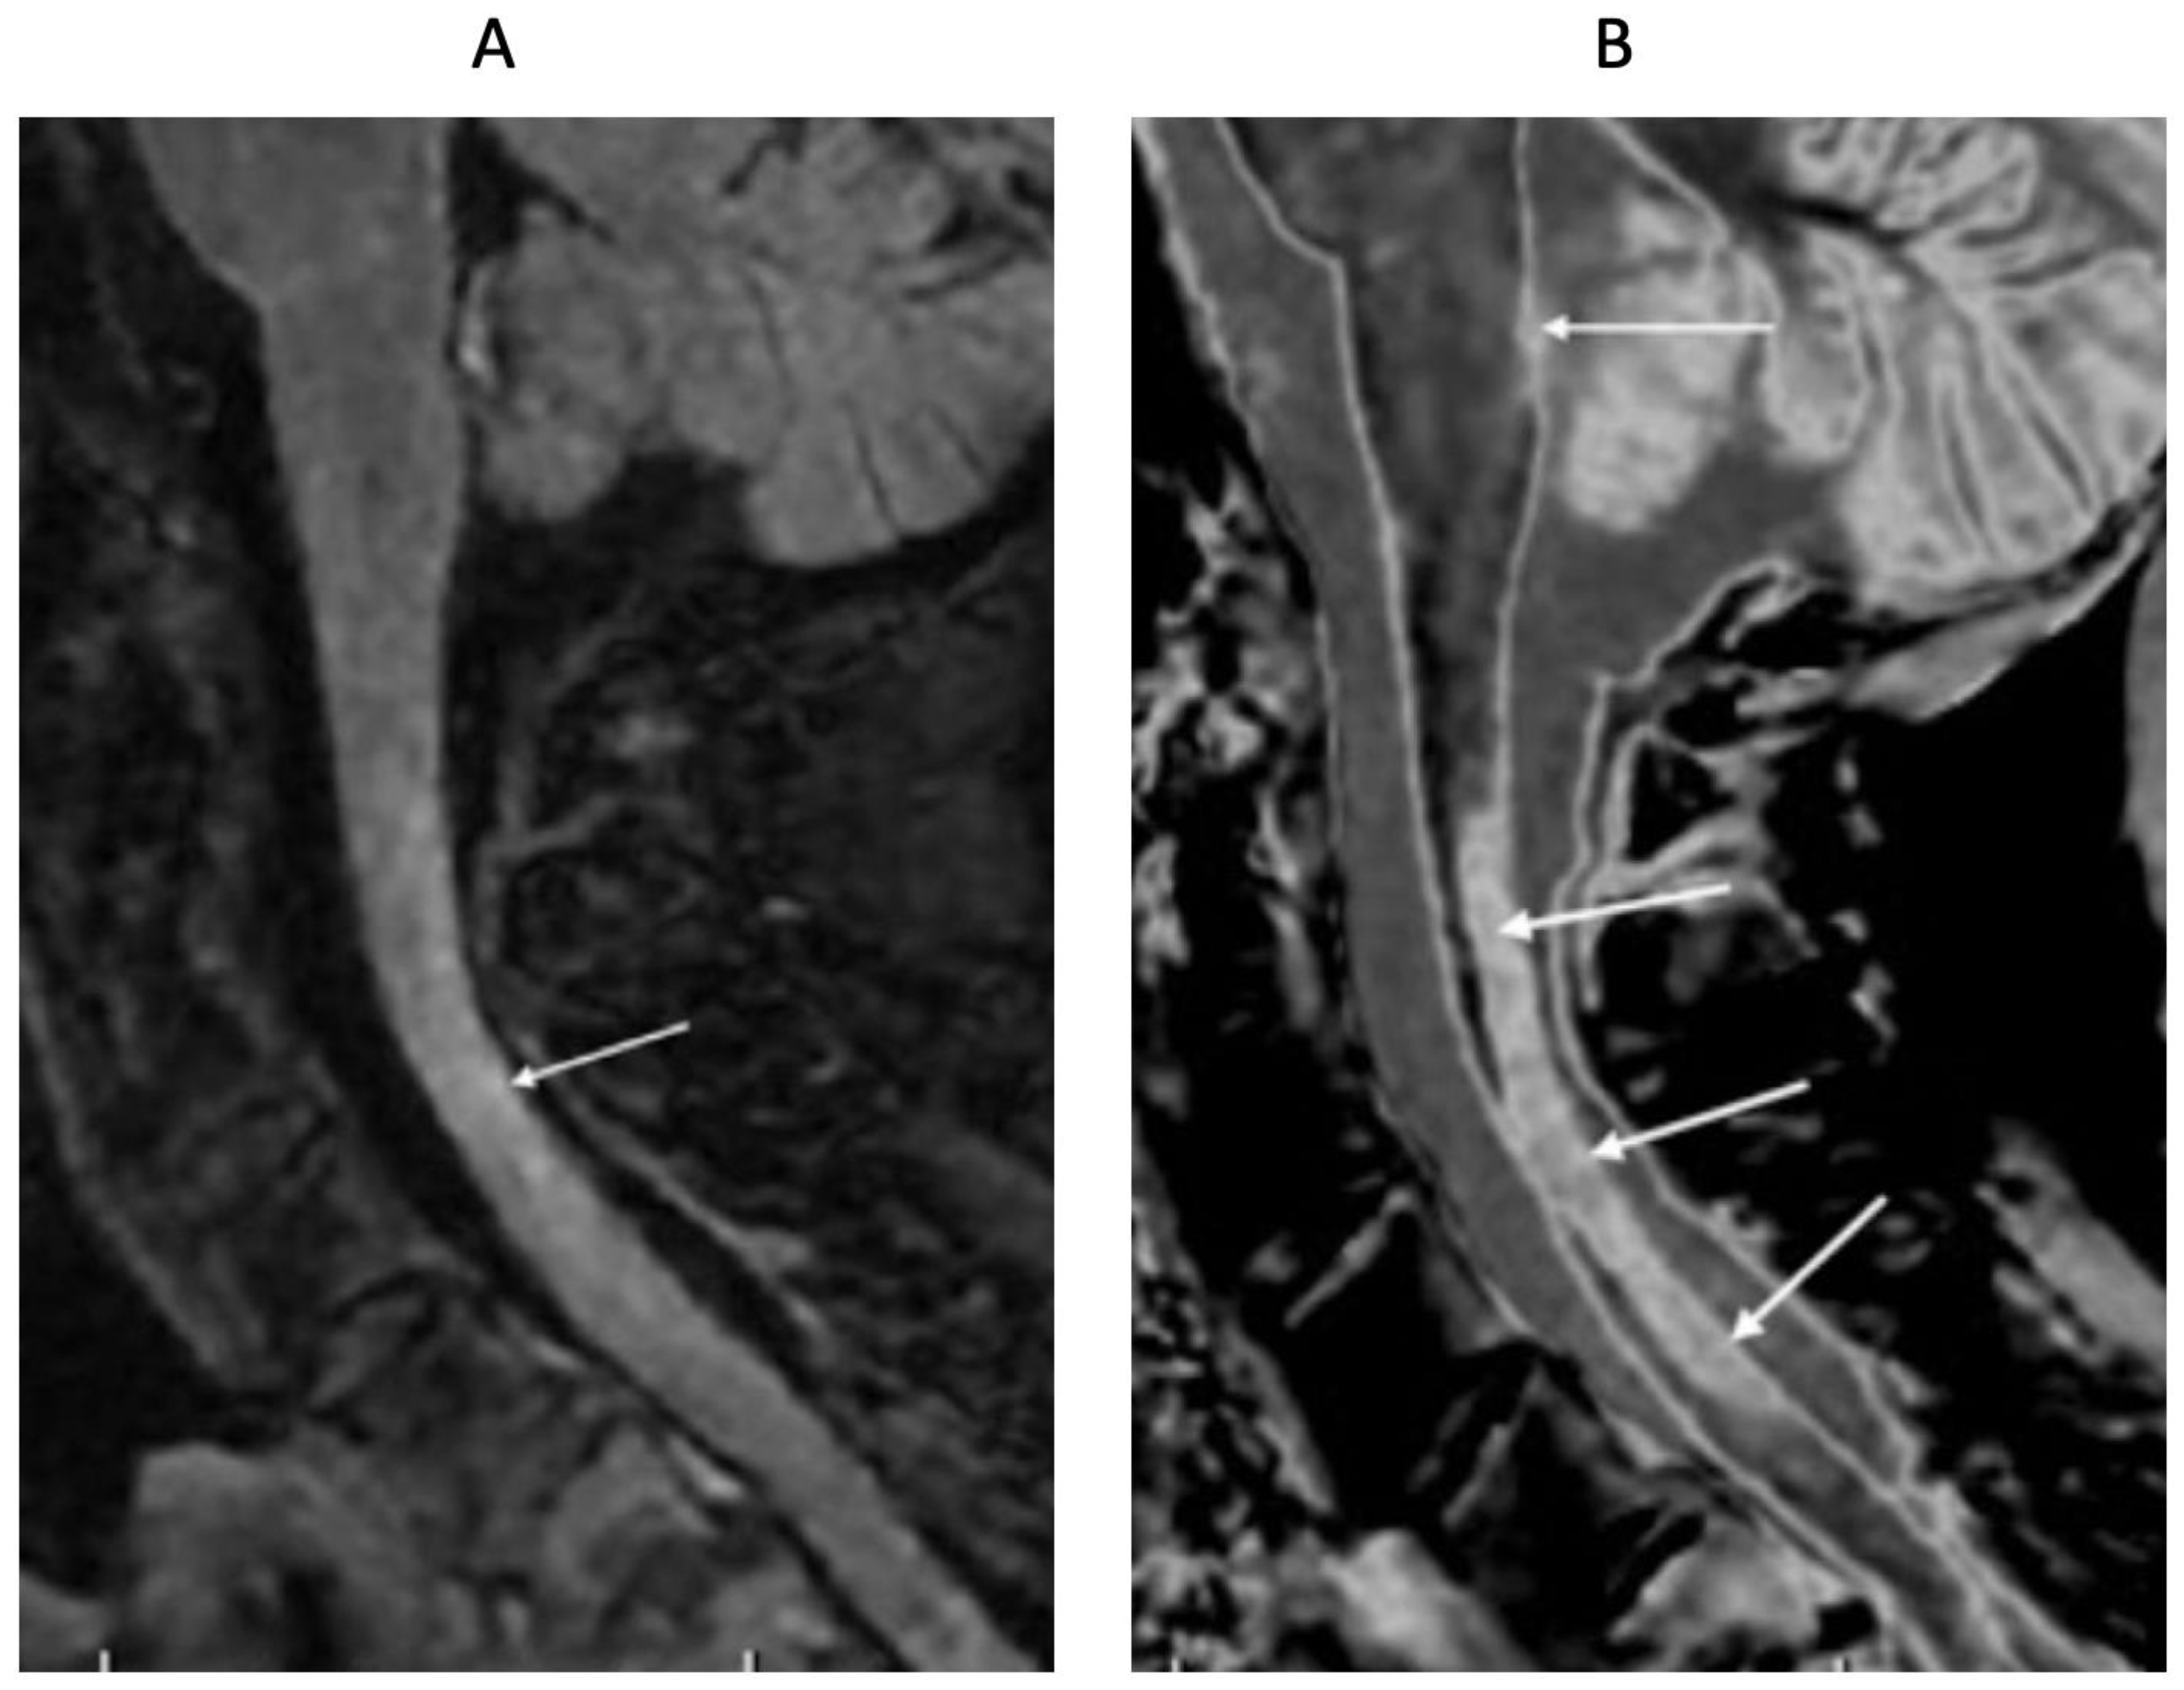

Figure 15 shows T2-FLAIR (Figure 15A) and wide mD dSIR (Figure 15B) sagittal images of the upper cervical spinal cord in a 43-year-old female patient with MS in remission. The T2-FLAIR image shows a poorly defined smudge of increased signal (white arrow). In the corresponding position, the dSIR image (Figure 15B) shows a high-contrast lesion with sharply defined boundaries, which is much more extensive than in (Figure 15A) (lower three arrows). An additional lesion is seen in the medulla on the dSIR image (highest arrow), but is not seen on the T2-FLAIR image.

Figure 15.

Forty-three-year-old female patient with MS in remission. Sagittal 3D T2-FLAIR (A) and 3D wide mD dSIR (B) images. The T2-FLAIR image shows a poorly defined area of increased signal in the cervical cord (arrow). The dSIR image shows a high contrast lesion with sharply defined boundaries, which is much more extensive than in (A) (lower three arrows). An additional lesion is seen in the medulla on the dSIR image (highest arrow) (B), but not on the T2-FLAIR image.